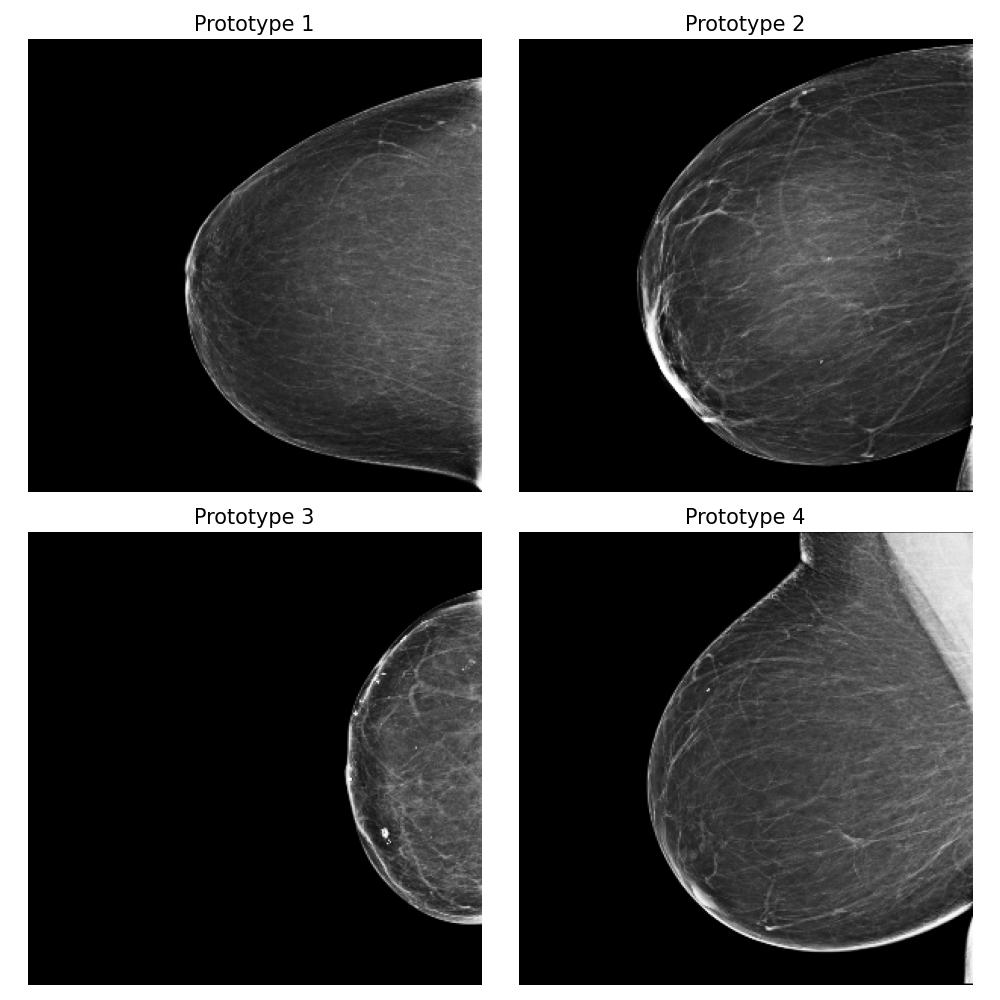

3.5.4 Case Study 2: Medical Image Data - Mammography Patient Population Dataset

In this case study, we assess the effectiveness of our proposed method in a realistic application, focusing on identifying differences between mammograms from two distinct patient populations. Specifically, we simulate a real-world scenario where users deploy models to analyze mammograms of women with varying tissue density distributions — a challenge commonly encountered when comparing premenopausal and postmenopausal patients or younger and older individuals. Premenopausal or younger patients often exhibit denser breast tissue, whereas postmenopausal or older patients often present with less dense tissue (Kim et al., 2020). This dataset evaluation step is crucial before deploying a clinical breast cancer risk detection model across different patient populations.

Dataset and

We use the publicly available EMBED dataset (Jeong et al., 2023). To simulate premenopausal and postmenopausal patient populations, we construct two datasets, and , by randomly sub-sampling from EMBED. Dataset comprises 27,224 mammograms from 8,456 patients with dense breast tissue (density category three in EMBED) and 21,675 mammograms from 7,841 patients in density category two. Dataset includes 27,224 mammograms from 2,715 patients with less dense tissue (density category one) and 21,675 mammograms from 7,797 patients in density category two (medium density). All mammograms were preprocessed to remove clinical markers and aligned such that the breast tissue faces left.

Forming the explanation

For this task, we implemented the “Prototype-summarization-based explanations” described in Section 3.5. We trained a binary vs classifier using the VGG19 feature extractor as backbone and learn four prototypes for each dataset. 97798 mammograms were used for training, and 24450 mammograms were used for testing.

Result

By examining the summarization prototypes shown in Figure 22, we identified tissue density as the primary difference between and . In mammograms, brighter areas correspond to denser tissue. Additionally, we observed that less dense tissue is often associated with larger tissue size. Without our proposed method, human users would need to manually analyze the dataset, which is a labor-intensive and time-consuming task, to reach the same conclusions.